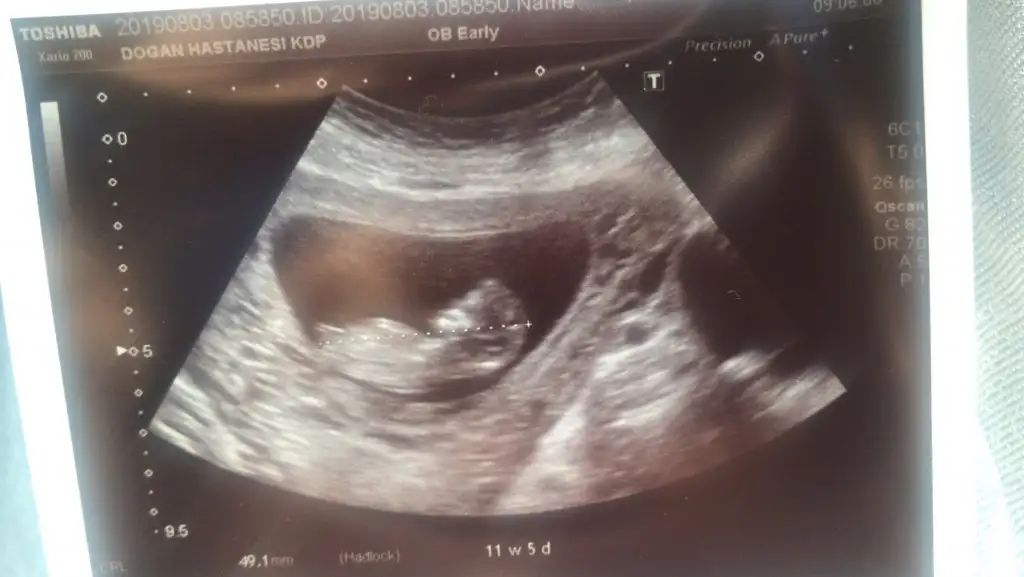

Normalde 10+5’im ama biraz hızlı büyümüşüm, bugün kontrolde 11+5 çıkınca enseme burnuma bile bakıldı. Poz verdim sizlere. Sizce kız mıyım erkek mi?

Canım nubu seçemedim çok net gözükmüyor usg de.ama kafa yapısını erkeğe benzettimCocoChanelmademoiselle canım bana da bakar mısın senin yorumunu merak ediyorum

Teşekkür ediyorum canım ben de hep erkek hissediyorum yaa ama kız diyor doktor inşallah sağlıklı sıhhatli olsun daCanım nubu seçemedim çok net gözükmüyor usg de.ama kafa yapısını erkeğe benzettim